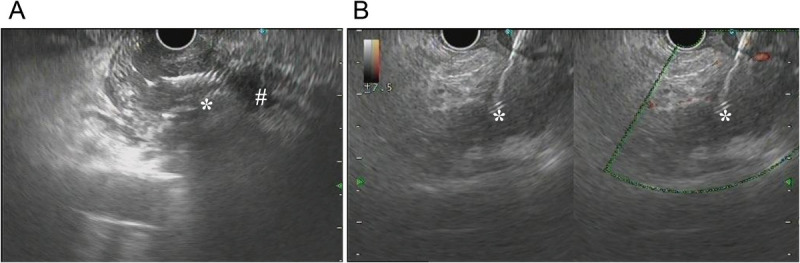

Abstract Image